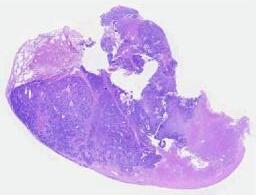

临床资料: 患者,女,34岁,病史:疑似“感冒”后咳嗽咳痰胸闷2周,影像CT:肺占位,生育史:孕3产3,一儿两女进行肺活检,两个月后心包多发结节,进行心包活检。